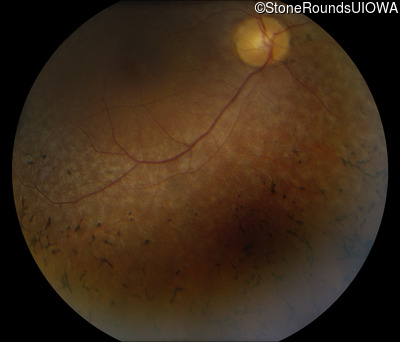

Fundus Photography - Right - 20/25

Exemplar

Fundus Photography - Right - 20/30 -1